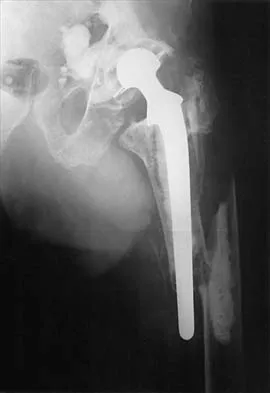

A 53-year-old patient is seen in the emergency department after sustaining a fall onto her left hip. A current radiograph is shown in Figure 40. What is the best treatment option?

Explanation

The patient has sustained a Vancouver B2 periprosthetic femoral fracture (a femoral fracture that occurs around or just distal to a loose stem, with adequate proximal bone stock). The stem is no longer fixed to proximal bone; therefore, retention of the femoral component is not recommended. Nonsurgical management is contraindicated because of the high risk of nonunion and malunion with significant component settling in the distal fragment and leg shortening. Revision femoral arthoplasty must attain distal fixation in adequate host bone, which is usually successful with a porous-coated cylindrical stem. Parvizi J, Rapuri VR, Purtill JJ, et al: Treatment protocol for proximal femoral periprosthetic fractures. J Bone Joint Surg Am 2004;86:8-16.